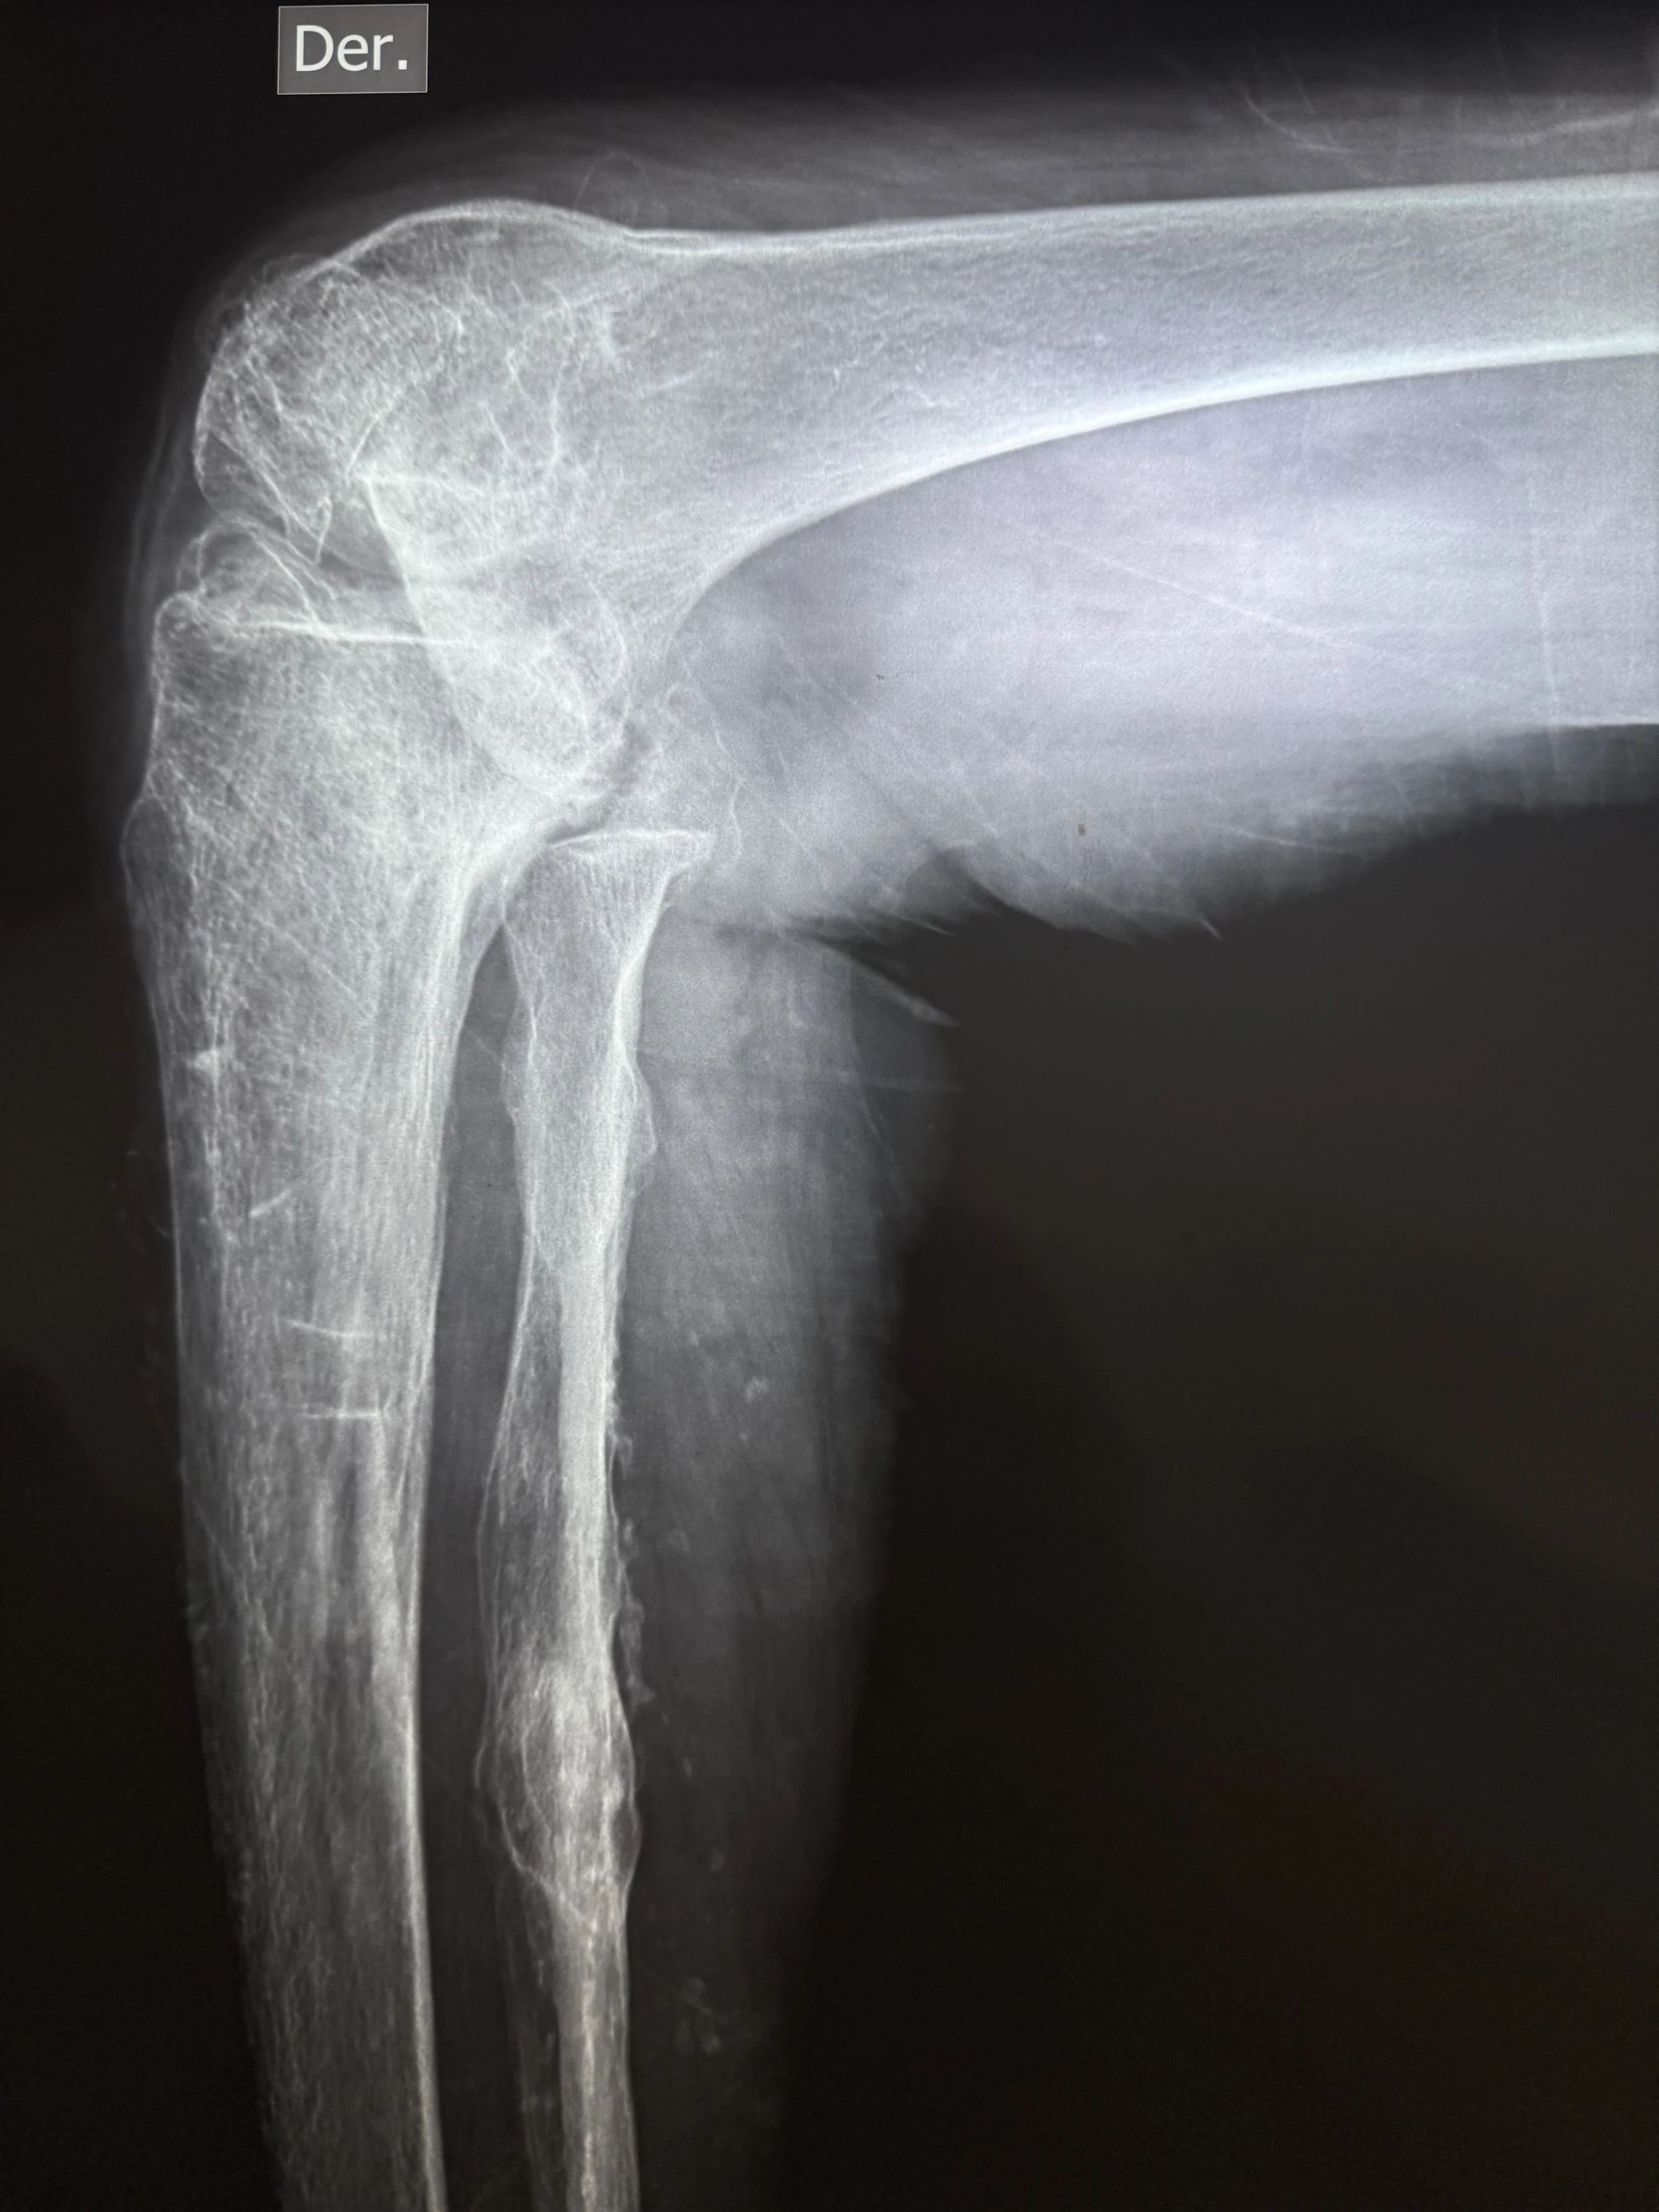

Today, we had the humble privilege of seeing over 100 patients in need of surgical care for hip, knee, foot, and ankle deformity. We will begin tomorrow with 6 operating rooms, 25 cases planned, 9 surgeons, 7 anesthesiologists, and 43 health care professionals working together.